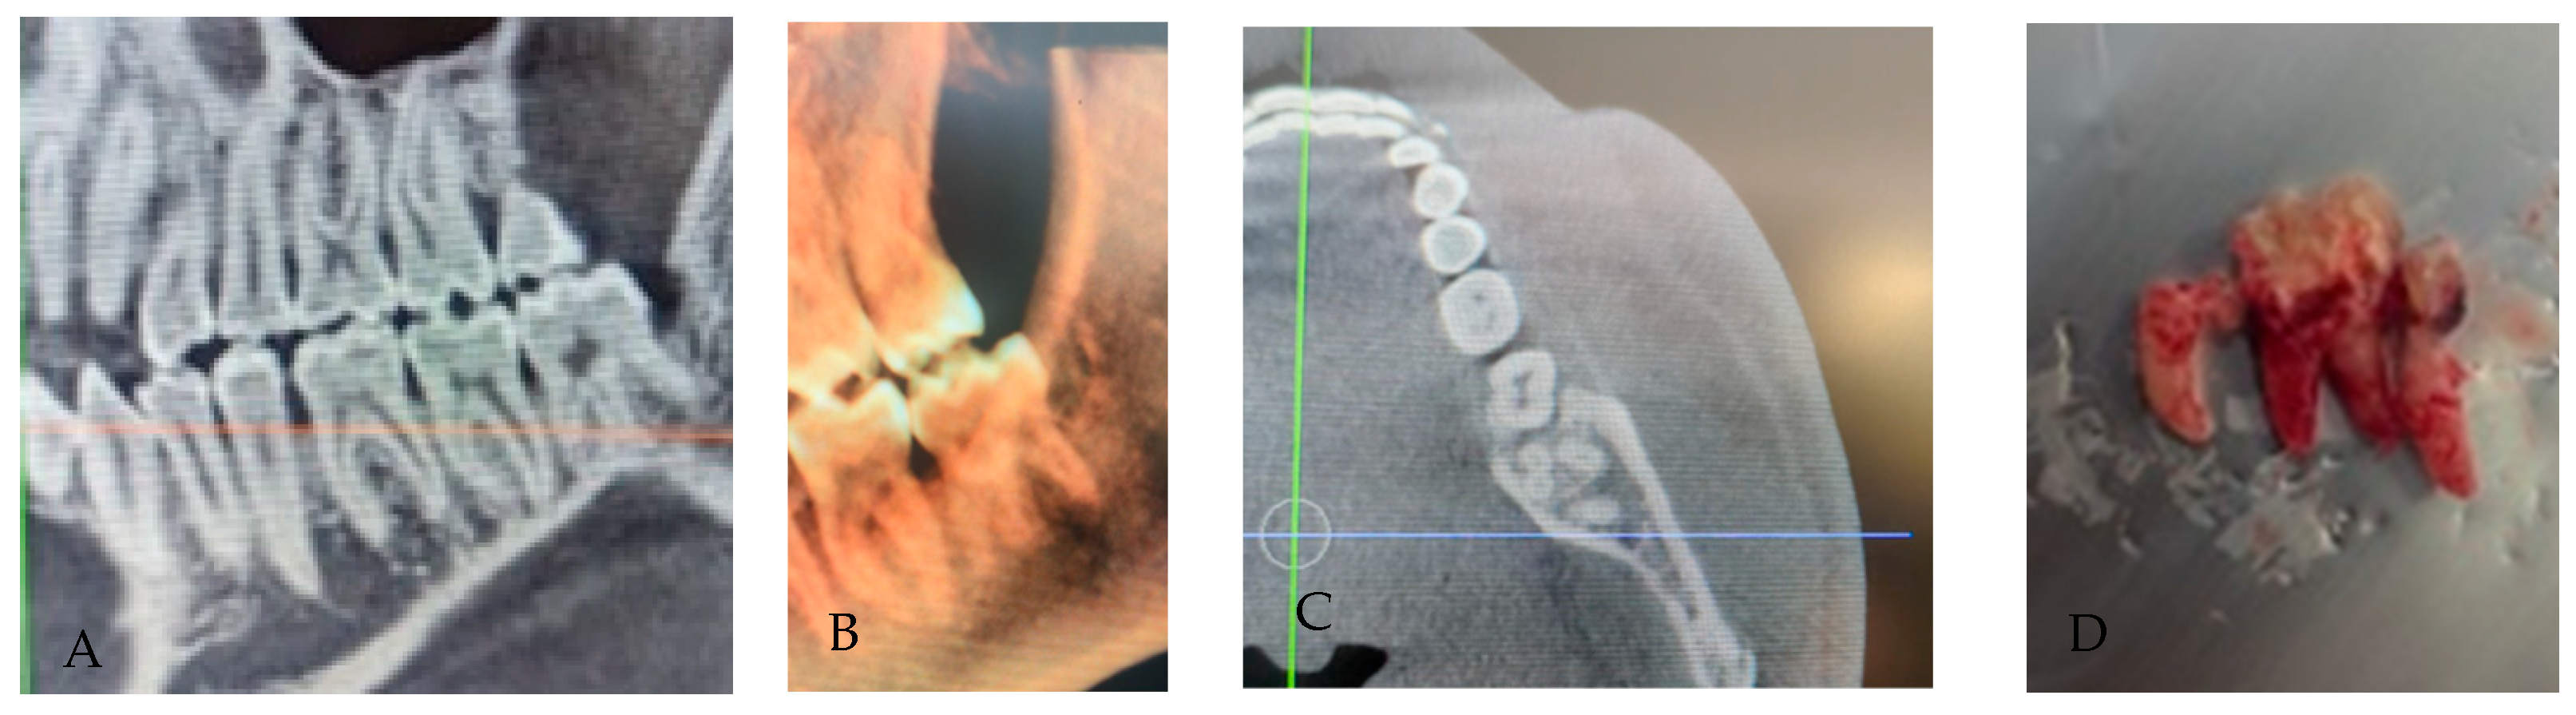

3.5. Root Fusion

3.6. C-Shaped Morphology

3.7. Dilaceration/Apical Curvature